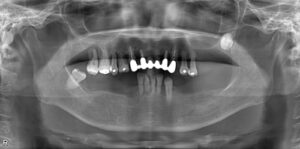

• 下顎大臼歯2本欠損症例

BEFORE AFTER 67歳女性/下2本/インプラント埋込手術 【治療内容】 右下第一大臼歯、第二大臼歯が根っこの先…